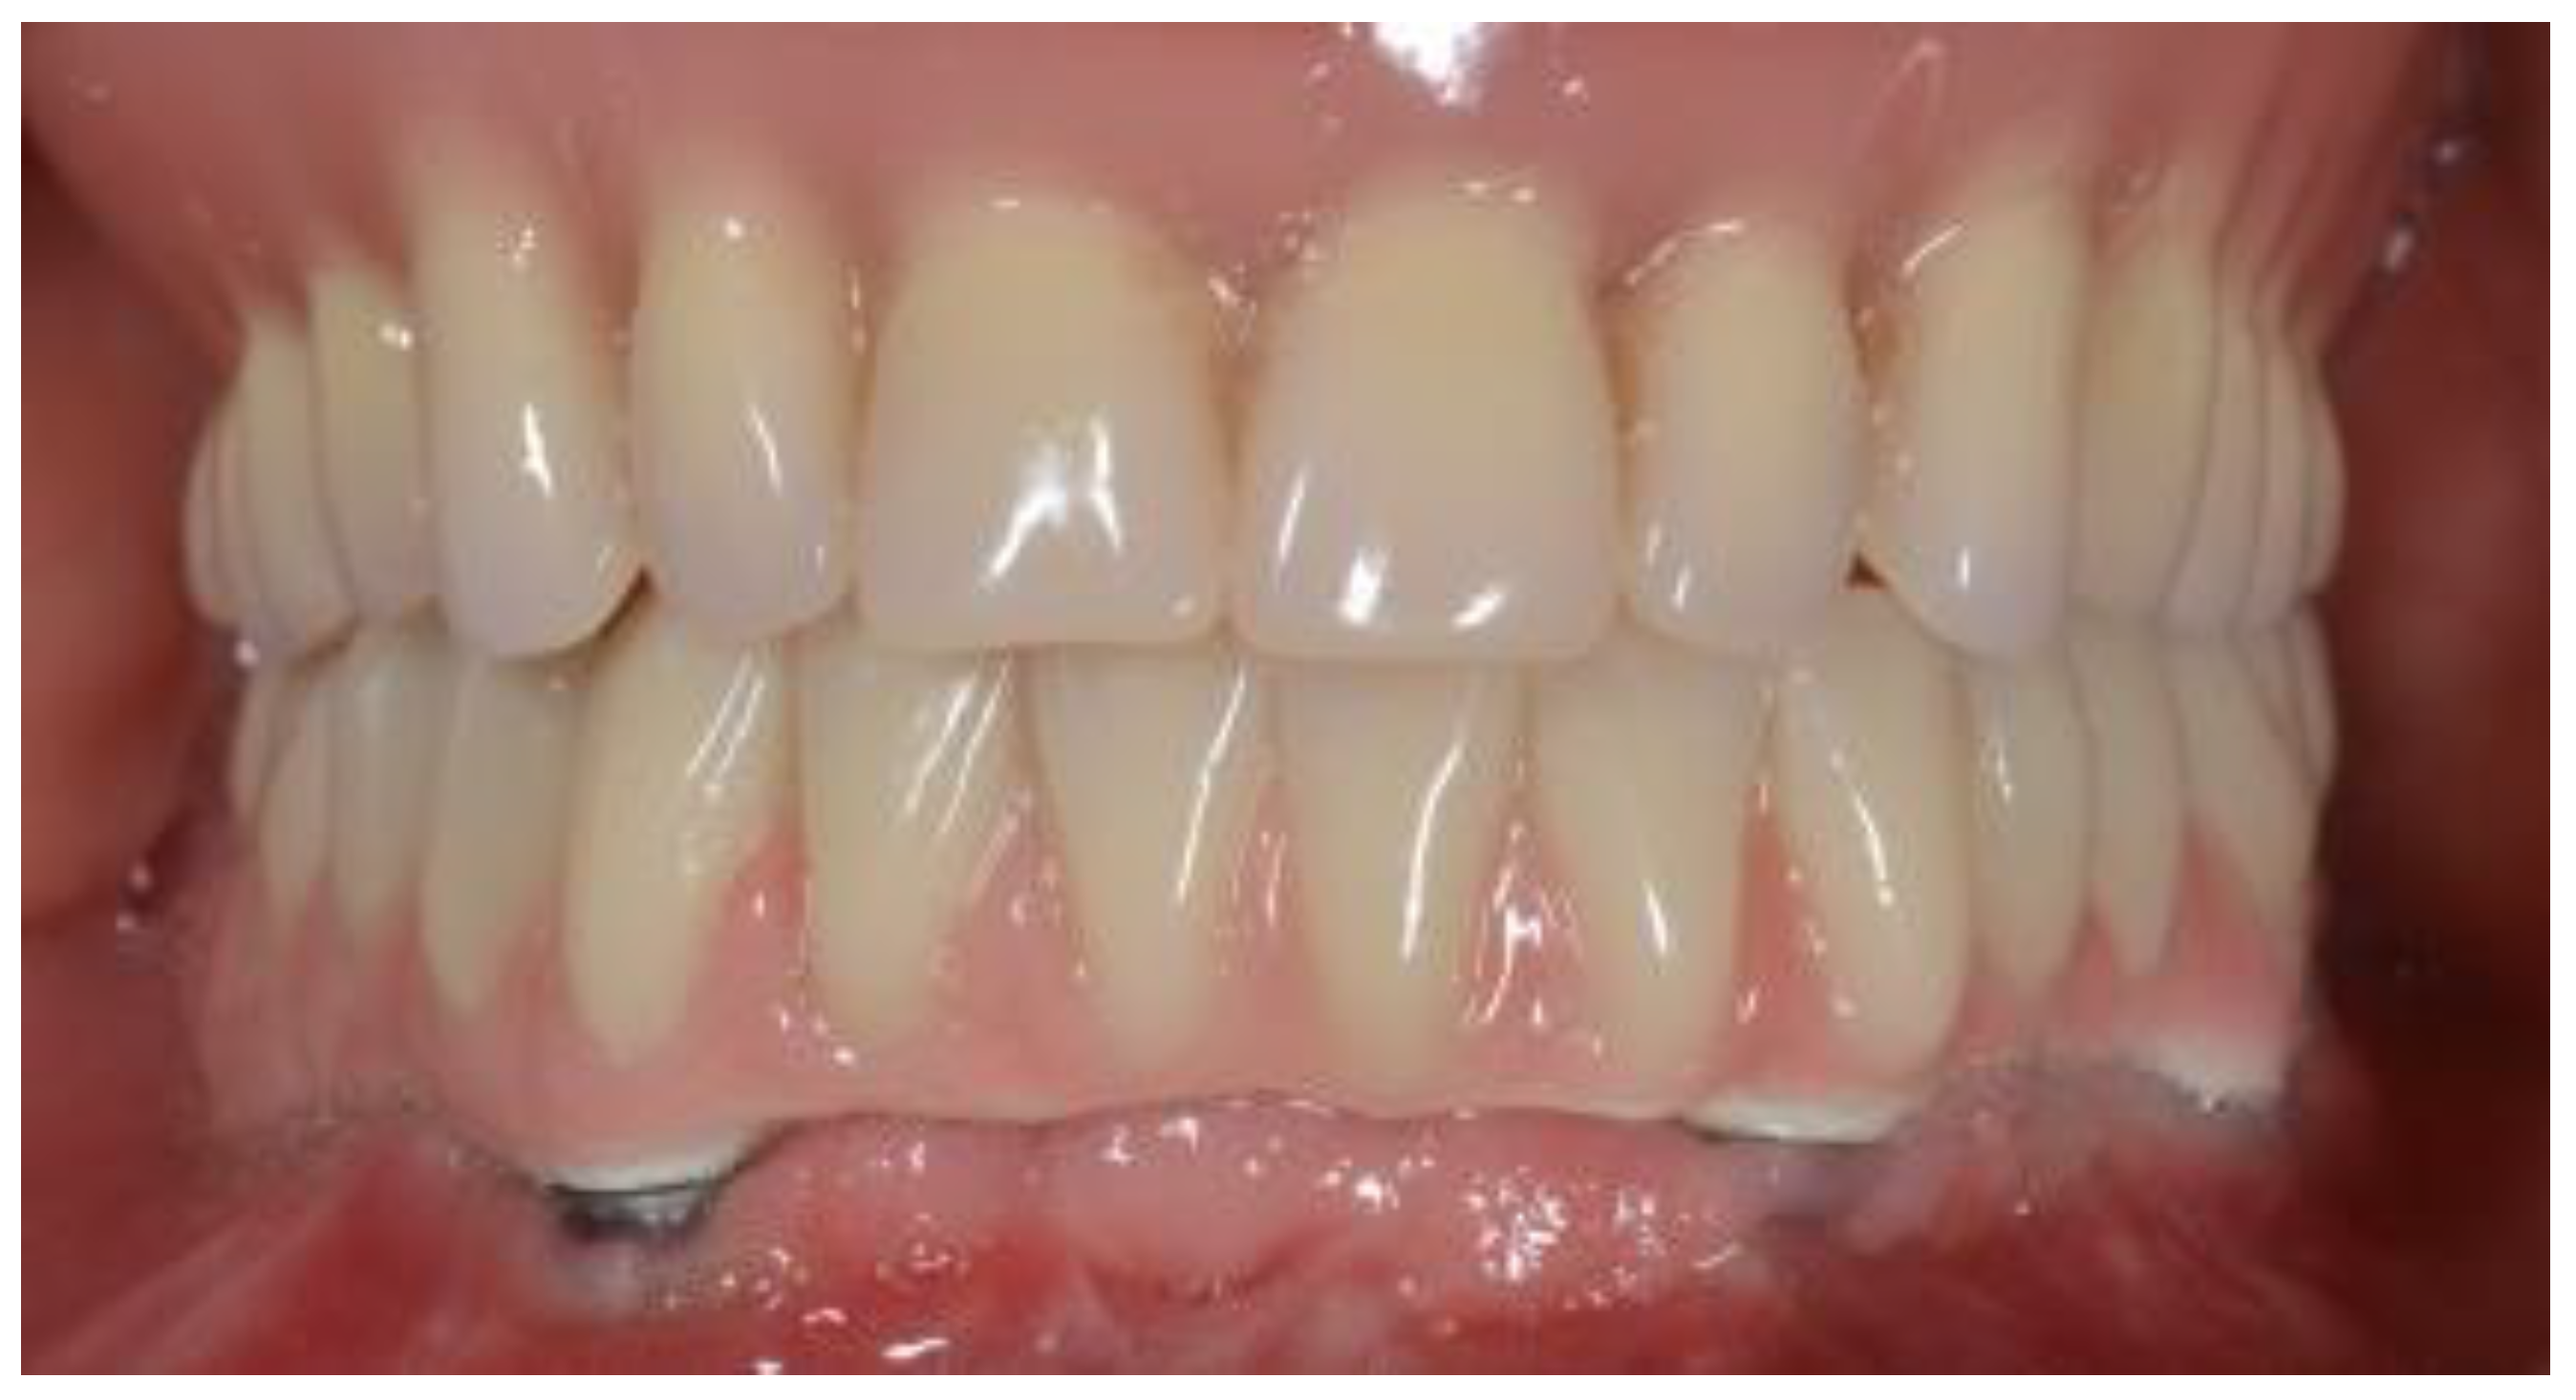

Edentulous Mandibles Restored with Fiber-Reinforced Composite Prostheses Supported by 5.0 mm Ultra-Short Implants: Ten-Year Follow-Up

2. Materials and Methods

3. Results